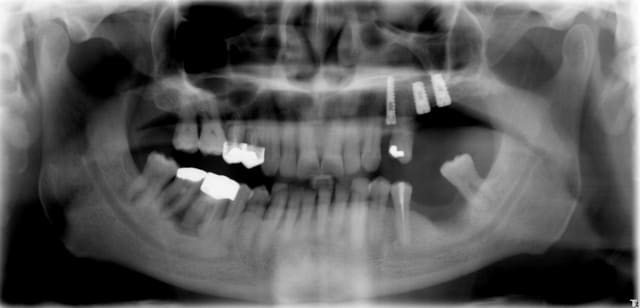

Patient 63 ans, 26 - 27 absentes et 24 à ext.

Mise en place de 3 implants Seven (MIS) en juillet 2006.

Au niveau de 27, je n'ai que 8mm sous le sinus, je fais donc un Summers avec de l'os autogène et du bio-oss.

Au niveau de 24, ext et mise en place immédiate de l'implant. La dent extraite étant en position très lingualée, la table osseuse vestibulaire présente une dépression assez marquée, surtout par rapport à la bosse canine voisine, ce qui risque peut-être de donner un aspect inesthétique au final , mais bon! tant pis! je suture le tout.

Et puis, je m'aperçois qu'il me reste pas mal de bio-oss non utilisé. Je me dis qu'au prix que ça coûte, ce serait idiot de le gâcher. Alors, je me suis dit qu'on allait donner un peu de volume en vestibulaire de 24. J'ai trouvé un passage latéralement entre 2 points de suture et j'ai littéralement "fourré" tout le bio-oss restant en regard de 24, mais sans aucune conviction.

Et aujourd’hui, j’ouvre pour mettre les piliers de cicatrisation, et je découvre sur la 24 une épaisseur de 4mm d’os superbe(du vrai os, pas un tissu néoformé quelconque) sur la table osseuse vestibulaire qui ne faisait que 2mm au départ, comme si on avait fait une greffe en onlay. Et en plus la vis de couverture était partiellement recouverte d’os.

J'ai une pano après pose des implants. Ca n’illustre rien, mais c’est juste pour présenter le cas.

voilà la pano

j'y connais pas grand chose,mais as tu la place de mettre un implant sur 24,vu le peu de place entre 23 et 25 ? on a l'impression que l'implant 24 rentre presque dans la racine de 25,ce doit être la radio alors!